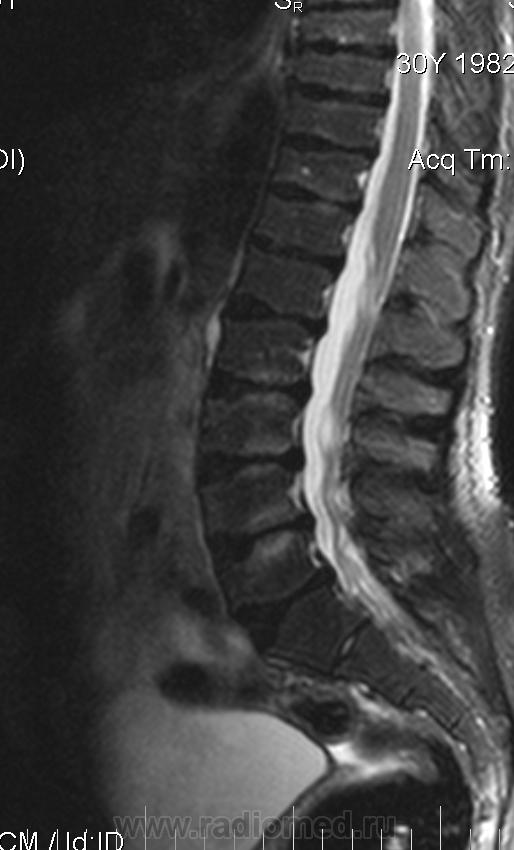

Мужчина 30 лет, рост 151см

Уважаемые колллеги, помогите, пожалуйста. Изменение формы тел позвонков. Остеохондропатия?

Изменения позвонков типичны для спондилоэпифизарной дисплазии.

Для спондилоэпифизарной дисплазии типична деформация позвонков по типу "переднего языка", платиспондилия, низкорослость, при Шойерман-Мау деформация позвонков другого типа.